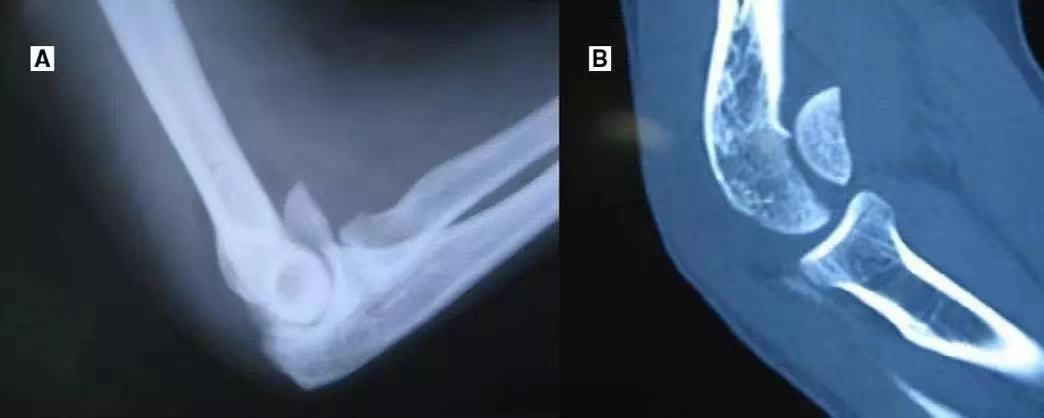

(9)尺骨鹰嘴骨折肘关节脱位:两者均有肘部疼痛,伸直位固定。但脱位为环周肿痛,弹性固定于135°,肘窝可扪及肱骨远端,肘关节主、被动活动均受限;X线示肘关节脱位,无骨折征。

(8)肱骨内上髁骨折肘关节后脱位:两者均有肘部疼痛、肿胀,伸直位固定。但脱位为环击肿痛,弹性固定于135°、肘窝可扪及肱骨远端,鹰嘴上方空虚,肘部呈靴状畸形;X线片示脱位、无骨折征。关节向后内或后外脱位,肱骨内上髁骨折常可合并肘关节向后内或后外脱位。